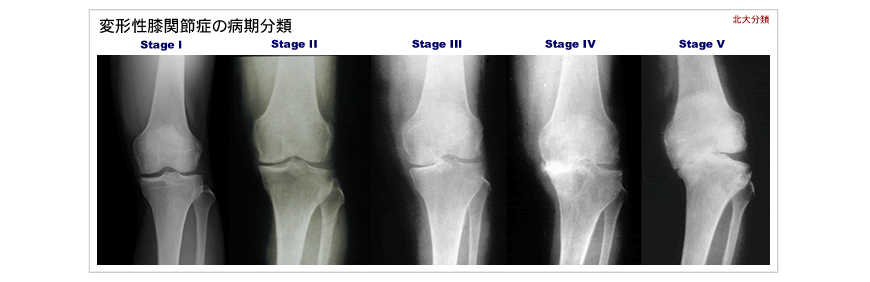

変形性膝関節症の病期分類

Stage Ⅰの方が主な対象

Stage Ⅱ-Ⅲの方が主な対象

Stage Ⅲ-Ⅳ で骨質がしっかりしていて、重労働従事者などが主な対象

Stage Ⅳ~Ⅴ の方が主な対象